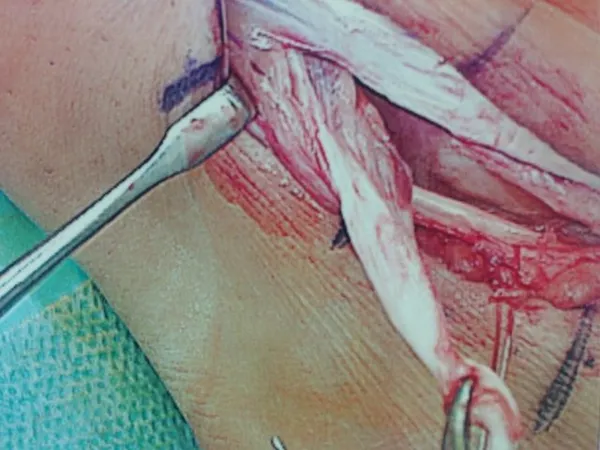

Peroneus Brevis Split Tear with Surgical Repair and Removal of Torn Tendon Portion. (below)

Partial Tear Peroneus Brevis Tendon. (below)

Removal of Torn portion and debulking of tendon. (below)